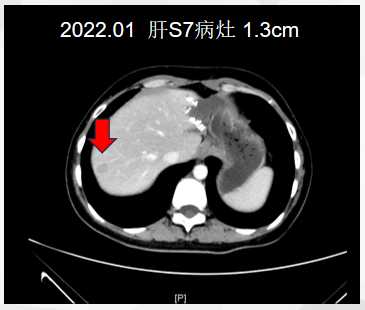

患者于2022年1月15日复查CT示:S4、S7新增转移灶,大者约1.3cm(图4)。